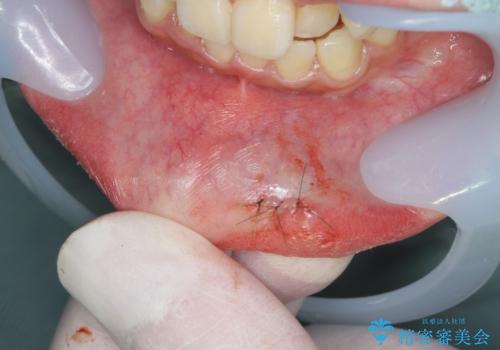

唇がたびたび腫れる 粘液嚢胞の摘出

- 下くちびるを、強くぶつけそれ以来たびたび半透明のドーム状の腫れを繰り返し治療を希望され来院されました。

粘液嚢胞(唾液の貯留によるふくらみ)は、外科的に小唾液腺を含めた摘出が適応です。

粘液嚢胞は膨らんだりつぶれてなくなったりを繰り返すので、膨らんできた頃合いに来院いただき、マイクロスコープ下で低侵襲な小手術を行います。

小さな傷跡が手術後には残りますが、極細の糸で縫うことで2週間ほど経てば傷口は綺麗に治癒します。

また再発の可能性もあるので経過観察が必要です。